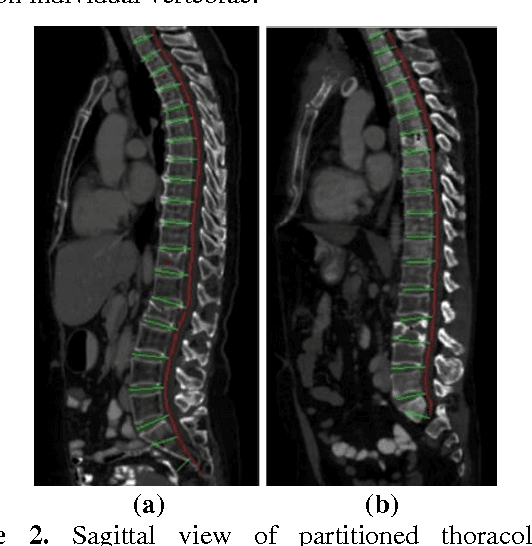

Abstract:Accurate spine segmentation allows for improved identification and quantitative characterization of abnormalities of the vertebra, such as vertebral fractures. However, in existing automated vertebra segmentation methods on computed tomography (CT) images, leakage into nearby bones such as ribs occurs due to the close proximity of these visibly intense structures in a 3D CT volume. To reduce this error, we propose the use of joint vertebra-rib atlases to improve the segmentation of vertebrae via multi-atlas joint label fusion. Segmentation was performed and evaluated on CTs containing 106 thoracic and lumbar vertebrae from 10 pathological and traumatic spine patients on an individual vertebra level basis. Vertebra atlases produced errors where the segmentation leaked into the ribs. The use of joint vertebra-rib atlases produced a statistically significant increase in the Dice coefficient from 92.5 $\pm$ 3.1% to 93.8 $\pm$ 2.1% for the left and right transverse processes and a decrease in the mean and max surface distance from 0.75 $\pm$ 0.60mm and 8.63 $\pm$ 4.44mm to 0.30 $\pm$ 0.27mm and 3.65 $\pm$ 2.87mm, respectively.

Abstract:The precise and accurate segmentation of the vertebral column is essential in the diagnosis and treatment of various orthopedic, neurological, and oncological traumas and pathologies. Segmentation is especially challenging in the presence of pathology such as vertebral compression fractures. In this paper, we propose a method to produce segmentations for osteoporotic compression fractured vertebrae by applying a multi-atlas joint label fusion technique for clinical CT images. A total of 170 thoracic and lumbar vertebrae were evaluated using atlases from five patients with varying degrees of spinal degeneration. In an osteoporotic cohort of bundled atlases, registration provided an average Dice coefficient and mean absolute surface distance of 2.7$\pm$4.5% and 0.32$\pm$0.13mm for osteoporotic vertebrae, respectively, and 90.9$\pm$3.0% and 0.36$\pm$0.11mm for compression fractured vertebrae.